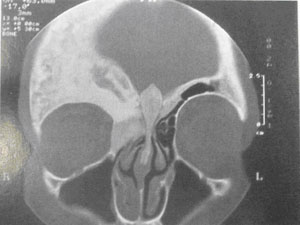

脑部CT扫描 主要是观察软组织的受累情况,以及周围软组织条件,重要肌肉,血管神经的比邻关系

图5 头颅冠状位CT

(来自plastic and reconstructive surgery)